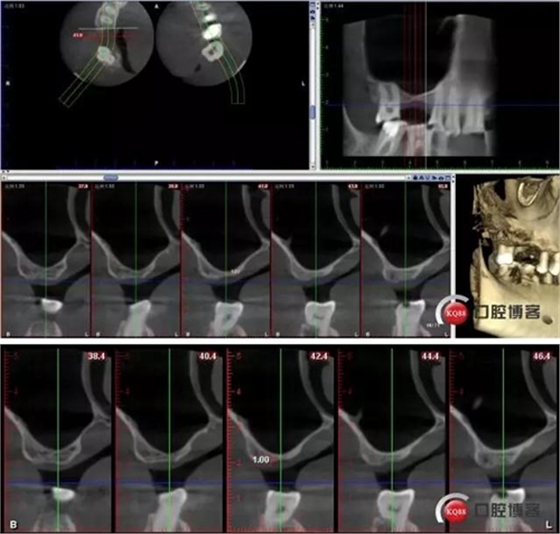

CBCT檢查:

16種植修復

用CAS鉆磨除牙槽嵴頂骨后水壓沖頂

術(shù)前術(shù)后CBCT對比: